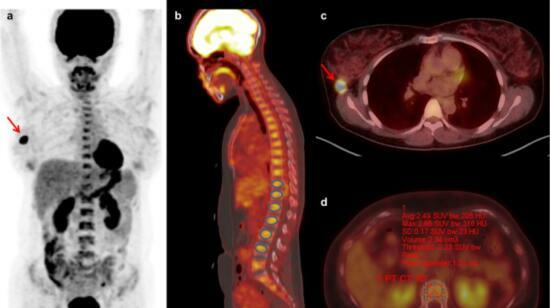

Hello Doctor, Seeking your opinion regarding a 71-year-old patient diagnosed with NSCLC favor squamous cell carcinoma (P40 diffuse positive, TTF1 negative) involving the right upper lobe. PET-CT shows a spiculated RUL lesion approx. 3.0 × 4.7 × 4.0 cm with SUV max 16.58. Mildly FDG-avid hilar/paratracheal nodes (SUV ~4.2) with some calcification noted. EBUS/TBNA from stations 4R, 7 and 11L showed no evidence of malignancy. Current staging documented as cT2bN1M0 (Stage IIB). Proposed plan is neoadjuvant chemotherapy followed by reassessment for surgery. Would appreciate guidance on: 1. Whether chemo + surgery appears the optimal curative-intent approach in this case. 2. Whether adding immunotherapy to neoadjuvant chemotherapy would significantly improve outcomes. 3. Whether current imaging/EBUS findings sufficiently support N1 staging or need further nodal evaluation. Thank you.

Importance of Pet-Ct in Diagnosing Cancer

A PET, or positron emission tomography, scan is a nuclear medicine imaging test. PET uses radioactive matter to show how organs and tissues are working and pinpoint disease. Combined with CT (computed tomography), PET/CT scans provide detailed 3D images of bone, tissue and organs for accurate ...